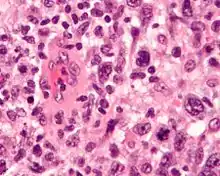

| Micrograph of an anaplastic large-cell lymphoma. H&E stain. | |

ALCL is defined based on microscopic histopathological examination of involved tissues which shows the presence of at least some ALCL-defining pleomorphic cells. These "hallmark" cells have abnormal kidney-shaped or horseshoe-shaped nuclei, prominent Golgi, and express the CD30 tumor marker protein on their surface membranes.[4] In 2016, the World Health Organization (WHO) separated ALCL into four types: ALK-positive ALCL (also termed ALK+ ALCL), ALK-negative ALCL (ALK− ALCL), primary cutaneous ALCL (pcALCL), and breast implant-associated ALCL (BIA-ALCL). WHO defined BIA-ALCL as an ALCL type provisionally, i.e. subject to redefinition if future studies should support such a change.[4][5]

ALK-positive ALCL is diagnosed by histological and immunological examinations of involved tissues, typically lymph nodes. These tissues have lymphoma-like infiltrates that have variable numbers of ALCL "hallmark" cells, i.e. cells with kidney- or horseshoe-shaped nuclei that strongly express CD30 as detected by immunohistochemistry and an ALK fusion protein as detected by fluorescence in situ hybridization.[11] These cells are scattered throughout the infiltrates. WHO classifies these infiltrates into 5 patterns: a common pattern consisting of large variably shaped cells with large nuclei that typically contain multiple nucleoli (60–70% of cases); a small-cell pattern consisting of small to medium-sized neoplastic cells with clear cytoplasm and "hallmark" cells that are concentrated around small blood vessels (5–10% of cases); a lymphohistiocytic pattern consisting of small neoplastic cells along with abundant histiocytes (10% of cases); a Hodgkin's-like pattern in which the architecture resembles the nodular sclerosis pattern of Hodgkin lymphoma (3% of cases); and a composite pattern consisting of two or more of the just described patterns (15% of cases).[9] Detection of circulating autoantibody against ALK supports the diagnosis.[10] Individuals with low levels of these autoantibodies are at an increase risk of relapsing after treatment.[9]

The histology of ALK-negative ALCL, similar to ALK-positive ALCL, consist of "hallmark" cells that strongly express CD30. Unlike ALK-positive ALCL, however, ALK-negative ALC does not fall into different morphological patterns. The histological of this disease may overlap with and be difficult to distinguish from other CD30-positive T-cell lymphomas or the nodular sclerosis form of Hodgkin lymphoma. Cases in which ALK-negative ALCL is not distinguishable from the latter lymphomas are best diagnosed as peripheral T-cell lymphoma not otherwise specified (PTL, NOS). The histology of ALK-negative ALCL may also overlap with tumors of non–T-cell lineage such as various carcinomas. The differential diagnoses of ambiguous cases may be helped by examining the tumor cells for the expression of certain marker proteins. For example, expression of CD56, MUC1 (also termed EMA for epithelial membrane antigen), and clusterin and strong uniform expression of CD30 support the diagnosis of ALK-negative ALCL over PTL, NOS, while variable CD30 expression and extensive expression of T-cell receptor proteins favor PTCL-NOS over ALK-negative ALCL. Detection of certain gene abnormalities (see next section) may also help distinguishing these diseases.[4]

Diagnosis

In most individuals with BIA-ALCL, the affected breast has a thickened capsule around the implant and effusion fluid between the capsule and implant. Neoplastic cells are located in and typically limited to the capsule and effusion. Histological examination of the capsules shows large anaplastic cells but cells with all the features of ALCL "hallmark" are often difficult to detect. In addition to these neoplastic cells, the capsule lesions contain, sometimes in a large excess that makes diagnosis difficult, a variety of non-malignant cells such as small lymphocytes, histiocytes, and granulocytes (the granulocytes are mostly eosinophils). The histology of palpable masses exhibit a different pathological picture: the tumor masses have multinodular areas that consist of necrosis or fibrous tissue interspaced with areas that consist of large neoplastic cells that have abundant cytoplasm and abnormally shaped nuclei within a fibrotic and chronic inflammatory cell background. Again, typical ALCL-defining "hallmark" cells may be difficult to find in these masses. The effusions show abundant, uniform-appearing, non-cohesive large cells with irregularly-shaped nuclei, prominent nucleoli and abundant cytoplasm.[27] The histology and pathological features of diseased lymph nodes and tissues outside of the breast implant are indistinguishable from those seen in ALK-negative ALCL. The neoplastic cells in the capsules, effusions, and tissues strongly and uniformly express CD30, CD4 (75–84% of cases), EMA (48–90%), CD43 (86–95%), CD45 (44–74%), and in a far fewer percentage of cases various other marker proteins. These cells do not express ALK and often lack the characteristic surface marker proteins of T-cells. Identification of the status of these markers helps diagnose the disease.[4]